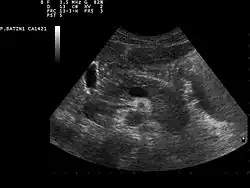

Zur Erkennung von Tumoren der Bauchspeicheldrüse werden bildgebende Verfahren wie Sonografie, Computertomographie, Magnetresonanztomographie sowie ein kombiniertes endoskopisch-radiologisches Verfahren, die sogenannte Endoskopisch retrograde Cholangiopankreatikographie, genutzt.[51] Darüber hinaus kann mittels Bauchhöhleneröffnung (Laparotomie) und -spiegelung (Laparoskopie) das Organ direkt beurteilt werden. Die Flexible Transgastrische Peritoneoskopie ist ein im Experimentalstadium befindliches Untersuchungsverfahren. Auch Pankreaspseudozysten, Pankreassteine (deren sicherer Nachweis erst nach Einführung der Röntgendiagnostik, etwa durch Arthur Mayo-Robson,[54] möglich wurde) oder Pankreasverkalkungen können mit den genannten bildgebenden Verfahren erkannt werden. Als brauchbarer Tumormarker hat sich CA 19-9 bewährt.[55]